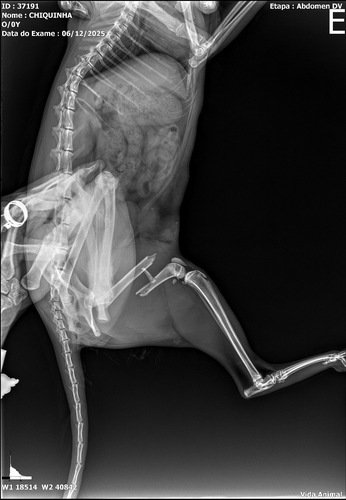

Chiquinha é uma gatinha muito querida que, infelizmente, foi atropelada e fraturou a pata. Para que ela volte a andar sem dor, é essencial realizar uma cirurgia para colocação de um pino no osso.

A consulta veterinária e o exame de raio-X já foram pagos, mas ainda falta arrecadar o valor do procedimento cirúrgico. Por isso criamos esta vaquinha solidária: cada doação nos aproxima do objetivo de garantir o melhor tratamento para a Chiquinha.